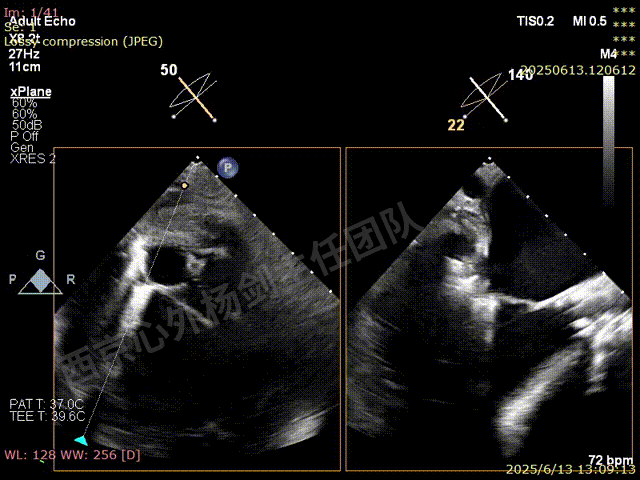

术前超声检查

TAVR术后,全心增大,二尖瓣反流重度,三尖瓣反流重度。中量心包积液。左室严重增大,标准图像调整困难。主动脉瓣位带支架人工瓣膜瓣叶启闭正常,主动脉瓣位人工瓣上血流速度Vmax 148cm/s,PGmax 9mmHg,Vmean 86cm/s,PGmean 2mmHg, VTI 34.7cm,瓣周反流(轻)。估测肺动脉收缩压约49mmHg;左室收缩功能明显减低。LVEF:23%,EDV:364ml,ESV:221ml。

彩色血流示:二尖瓣反流缩流颈彩宽6.6mm,面积17cm²,容积30ml;二尖瓣瓣口面积6.6cm²,瓣环内径:左右径34mm,前后径34mm。2区瓣叶长度:前叶36mm,后叶20mm,叶环比1.6. 三尖反流面积17.2cm²,容积33ml,Vmax 291cm/s,PGmax 34mmHg。